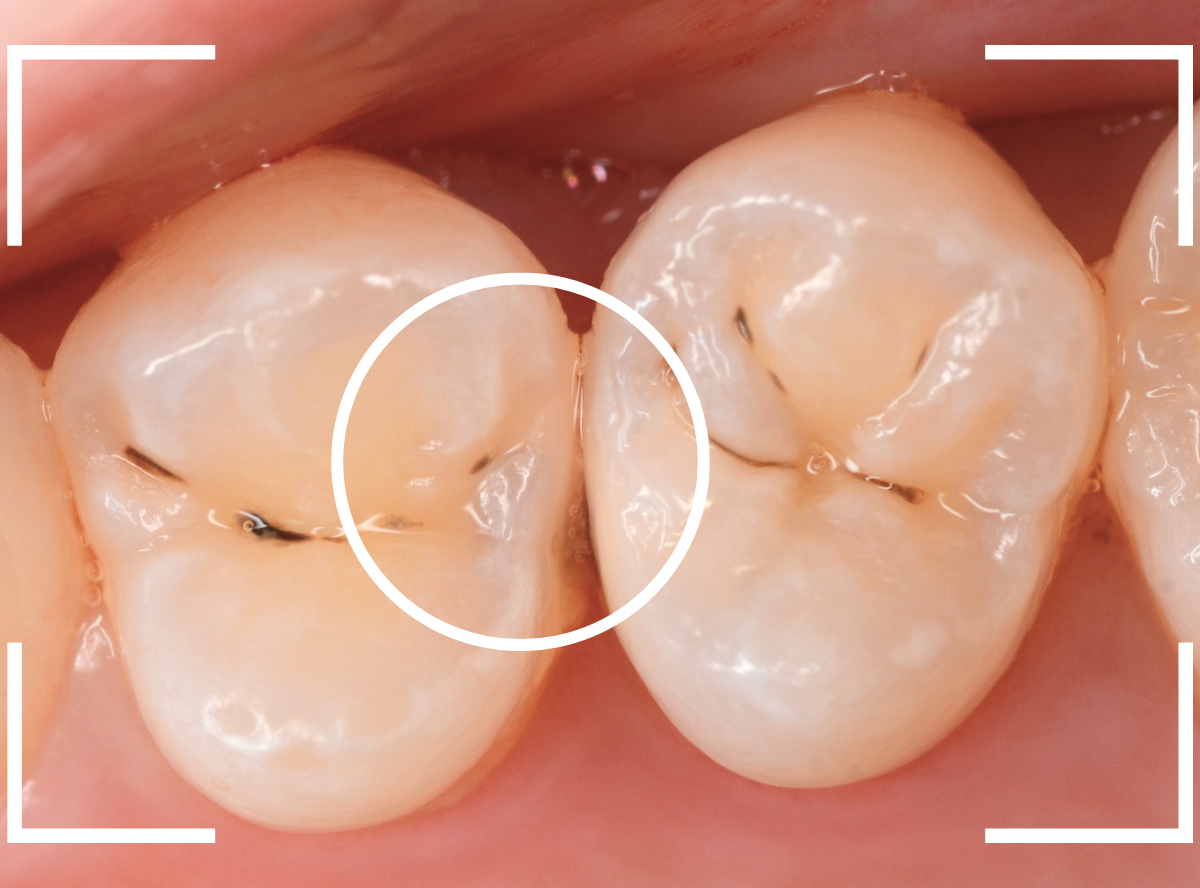

Case.22 痛みはないけど、歯のすきまから大きな虫歯

上の小臼歯の間が虫歯になっていた患者さんです。

症状はありませんし、見た目からも虫歯があるかはわかりませんでした。

レントゲン写真で確認します。

赤い線が虫歯、青い線が歯の神経です。

歯のすきまから両側に虫歯が大きく広がっているのが確認できます。